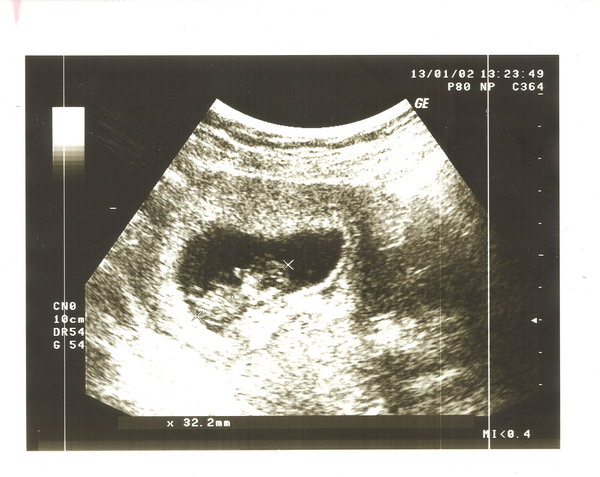

Megvolt az első UH-m 2-án (betöltött 10 héttel). 32.2 mm-es a BABICSEKEM. Mellékelem a fotót!

Kép